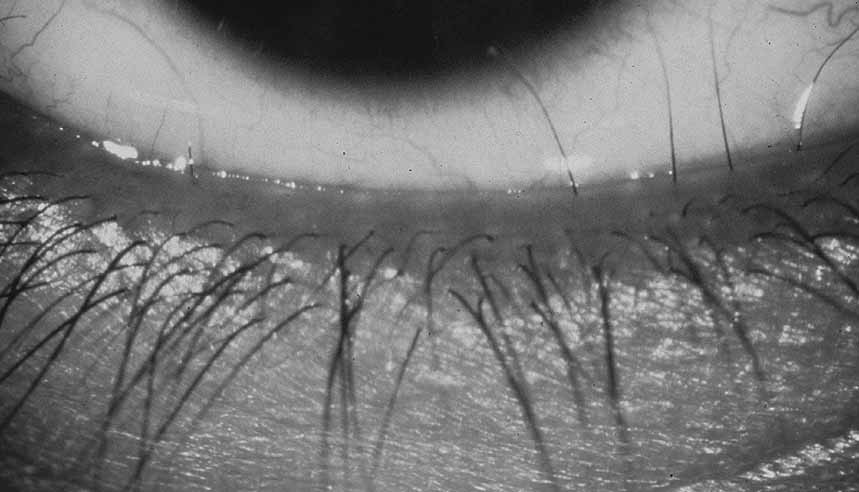

Persistent hyperplastic primary vitreous (PHPV) or persistence of fetal vasculature (PFV) is a complex malformation of the eye characterized by the presence of remnants of the hyaloid and of the tunica vasculosa lentis systems of blood vessels, together with proliferation of fibrovascular tissue behind the lens, and variable degrees of posterior pole and/or anterior retinal dysplasia.83,84 The eye in PHPV is generally microphthalmic but can be enlarged with accompanying myopia.85 Although PHPV primarily affects the posterior part of the eye, the ciliary body, iris, and lens are involved to a variable extent. In the typical case, ciliary processes are elongated and converge to a plaque of retrolental fibrovascular tissue that may involve the lens capsule proper (Fig. 4). The lens may be completely clear or may be cataractous. The fibrovascular plaque may adhere to the posterior lens capsule and vessels can invade the lens—a finding pathognomonic of PHPV. The retrolental membrane may contain adipose tissue, cartilage, and smooth muscle tissue. This is thought to be the result of metaplastic changes in tissues of mesenchymal origin. In a series of 47 eyes, Font et al. found adipose tissue in 10 and cartilage in one.86 The peripheral retina may also be drawn anteriorly into the retrolental membrane. In what has been referred to as “posterior PHPV,” the retina around the disc is pulled up into the posterior vitreous and is thrown into folds that may involve the macular and lead to poor vision. The retina is generally normal in structure, but dysplastic changes have been described. Vitreoretinal traction may lead to retinal breaks and detachment. The fellow eye in PHPV is usually normal but may have a Mittendorf dot or, rarely, one of other abnormalities.

|

PHPV is unilateral in approximately 90% of cases. The globe varies in size from normal to moderately decreased, being slightly smaller than normal in the majority of cases. The cornea is clear. The anterior chamber is shallow in smaller eyes because of anterior displacement of the iris/lens diaphragm; this predisposes patients with PHPV to angle-closure glaucoma, which usually develops later in life. Lens extraction prevents secondary angle-closure glaucoma. The iris may be normal but frequently shows small notches at the pupillary margin, where iridohyaloidal vessels were located in the developing eye and failed to regress as the iris matures and the tunica vasculosa lentis resorbs. Patent iridohyaloidal vessels may be observed to course over the anterior iris surface, the pupillary margin, and the posterior iris surface to anastomose with vessels in the retrolental membrane. These iridohyaloidal vessels are characteristic of PHPV.